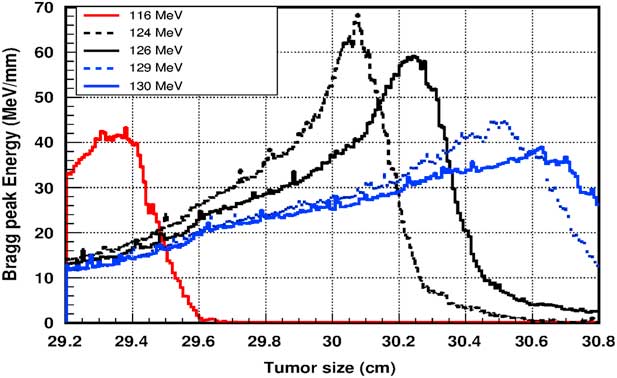

Figure 5 shows the plot of the deposited energy of a monoenergetic proton beam along the tumour size. As this figure shows, to surround completely a such tumour we should use a proton beam energy, ranging between 116 and 126 MeV. For this range energy, the Bragg peak energy is around 40 MeV and the half-value width for each Bragg peak is about 50% of the tumour size. The effect of adding gold in the tumour on the Bragg peak energy is shown in Figure 6. In this figure, we notice that the Bragg peak is localised in the tumour for the proton beam energy ranging between 116 and 130 MeV. The Bragg peak energy at the centre of the tumour is greater than without GNPs, in this case, with the presence of GNPs, the proton therapy is enhanced up to 75%, this is due to the concentration of GNPs at the centre of the tumour. Moreover, for high proton beam energy like 130 MeV, the width at half height of the Bragg peak is around of 75% of the tumour size. Comparing with previous results, the presence of GNPs in the tumour makes the width at half height of Bragg peak larger. This result shows that adding GNPs in tumours makes the proton therapy easier in clinical medicine and presents more benefit. Similarly in Figure 7, we plotted the deposited energy in the tumour with the presence of nanoplatinum materials. In this figure, the Bragg peak is localised in the tumour for the proton beam energy ranging between 116 and 132 MeV. Comparing with previous results, the width at half height of the Bragg peak is spread over 85% of the tumour. Moreover, the deposited energy at the centre in the tumour is almost double comparing with the same results in Figure 6. In the case of the use of silver NPs during this therapy, the plot of the deposited energy has the same shape as in the case of the use of GNPs (see Figure 8).

Figure 6 The deposited energy of a monoenergetic proton beam into the tumour with adding gold nanoparticles. Notes: The proton beam energy is ranging between 116 and 130 MeV.